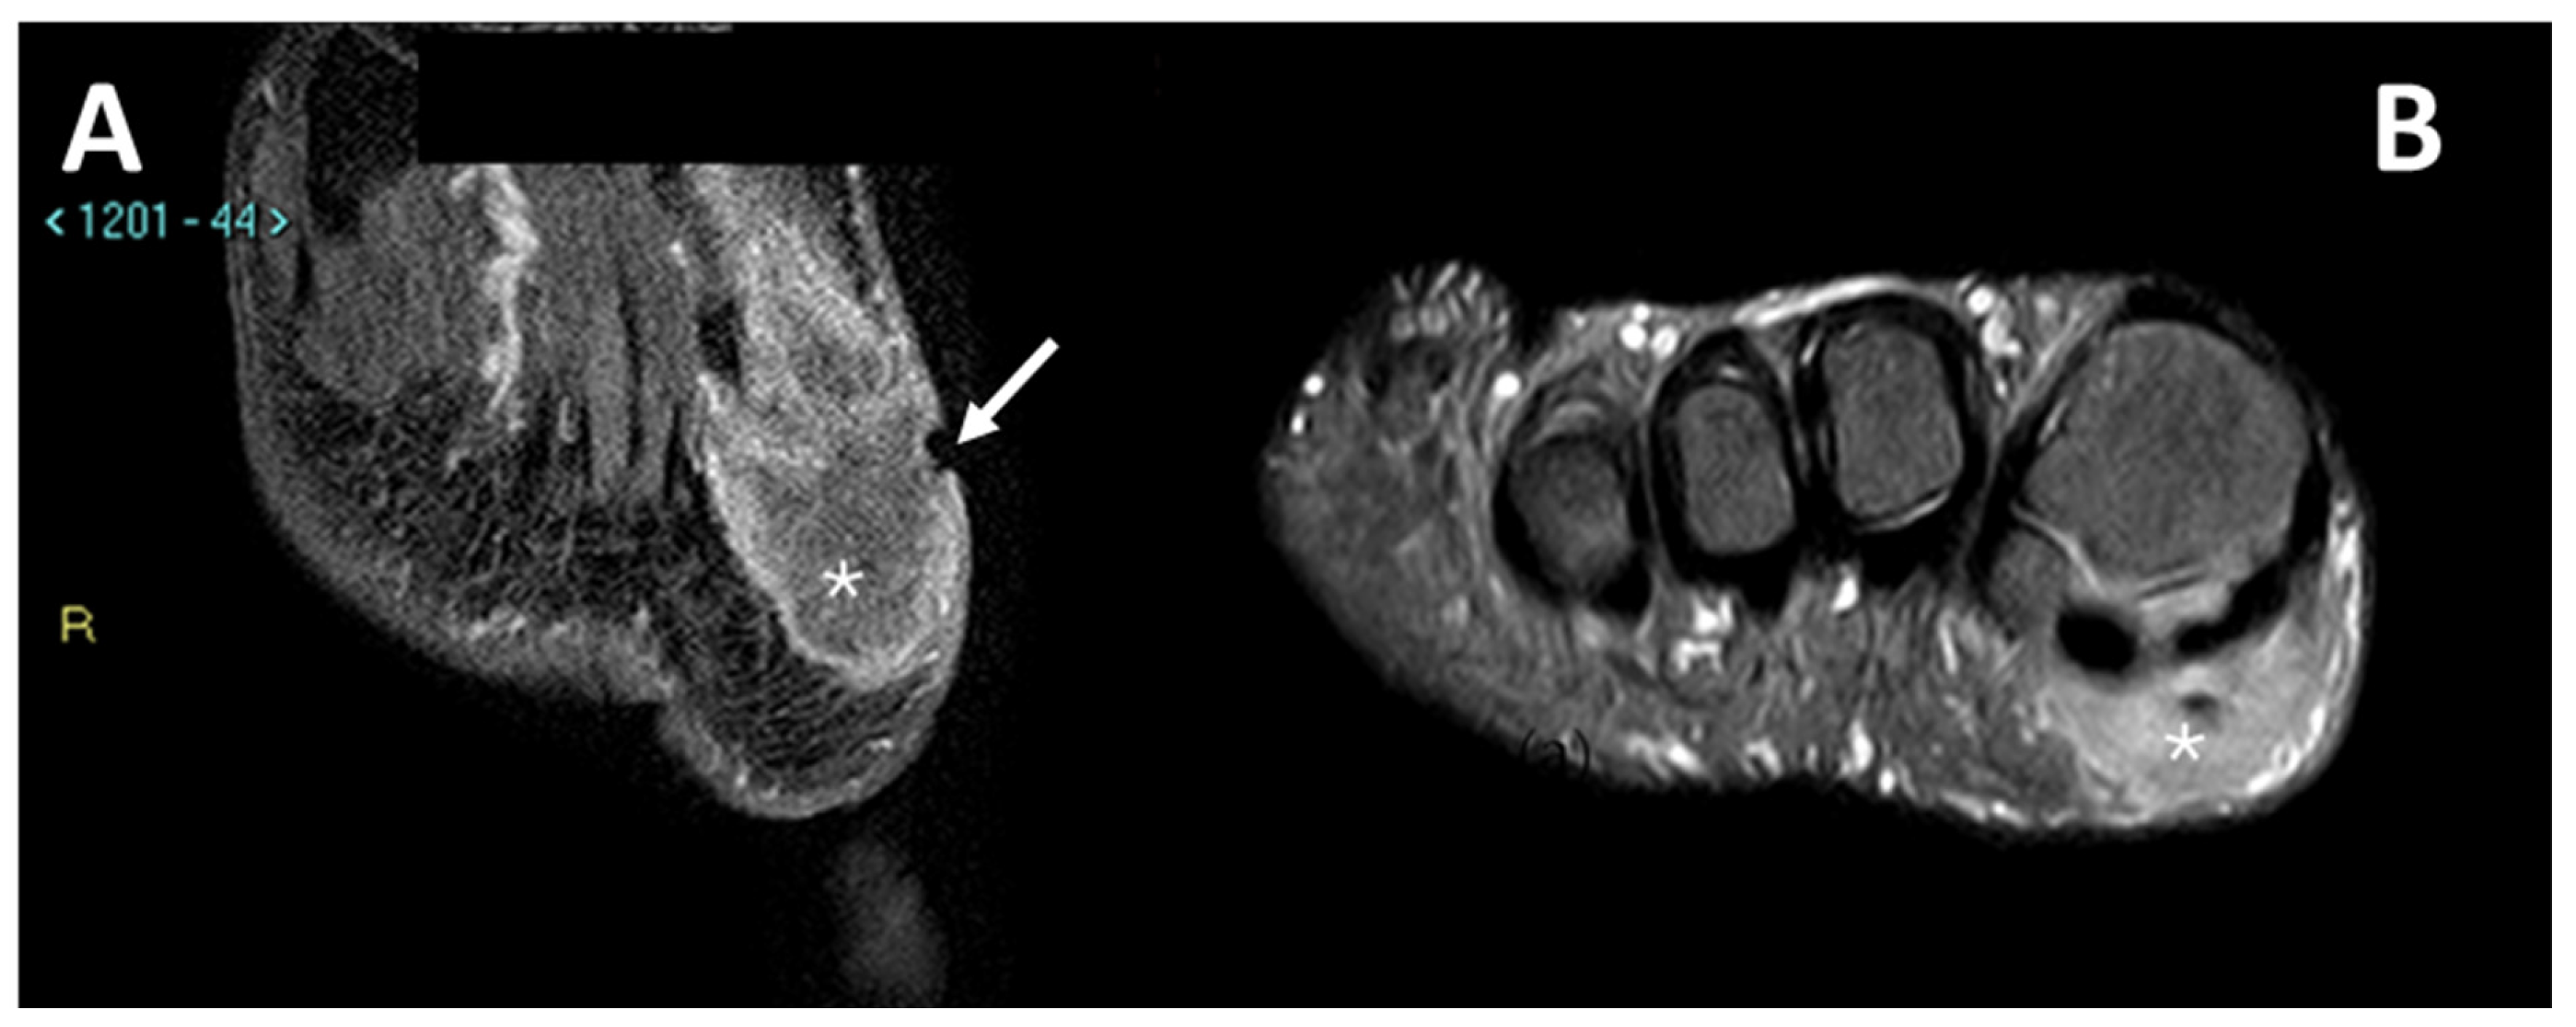

3.3.2. Macroscopic Necrosis (Assessed with MRI or CECT)

3.4. MRI Features

3.4.1. General MRI Features